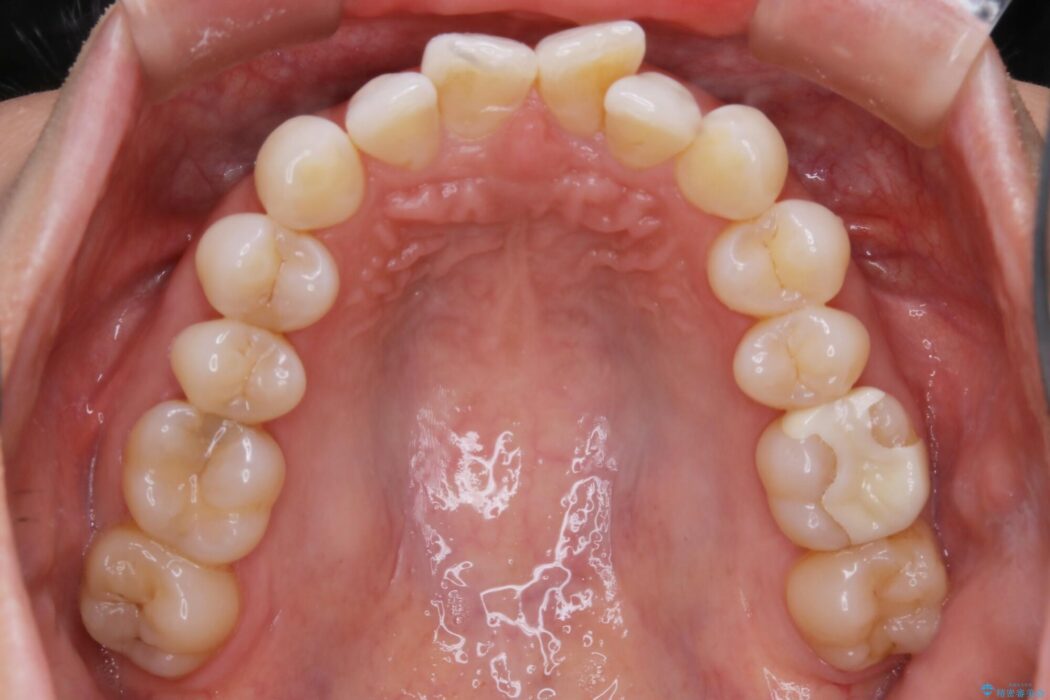

前歯のガタつきの治療を目的に来院されました。

主訴としては矯正治療にて歯列を整えることでした。

噛み合わせも改善され、一番最初の目的であった歯列もきれいに整いご満足いただけました。